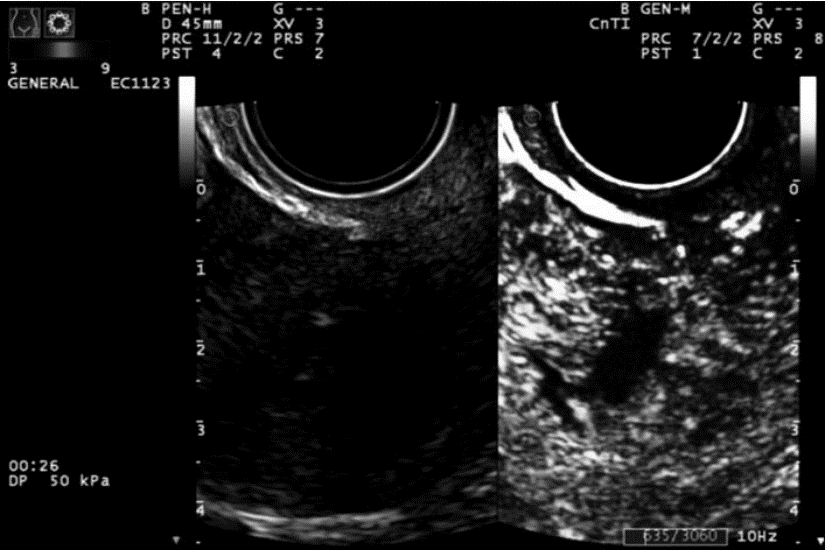

2 结果CDFI正确诊断切口妊娠和下段妊娠分别为17例、14例(图 1、图 2),CEUS正确诊断切口妊娠和下段妊娠分别为19例、20例(图 3、图 4)。CDFI、CEUS、CDFI及CEUS联合在切口妊娠与宫腔下段妊娠的鉴别诊断中差异具有统计学意义(P<0.05)。见表 1。

![]() |

| 图 4 CEUS显示孕囊周围呈不均匀强化,未见其与子宫下段前壁峡部相连续 |

CEUS检查简便、快捷,不受角度及呼吸运动的影响,可清楚显示微血管和组织的血流灌注情况[8],可为切口妊娠的鉴别诊断提供更多的信息,从而提高切口妊娠的诊断准确度。本组CEUS诊断切口妊娠的敏感度90.5%,特异度83.3%,其敏感度与CDFI相似,而特异度较CDFI增高。笔者观察到宫腔下段妊娠的CEUS表现与切口妊娠不同,宫腔下段妊娠时CEUS可见子宫前峡部肌层与孕囊之间的弧形无强化间隙,且绒毛增强时间晚于切口妊娠组,本组20例宫腔下段妊娠绒毛开始增强时间18~38 s,(26.3±7.1)s,19例切口妊娠绒毛增强时间11~23 s,(16.1±4.3)s,两者差异具有统计学意义(P<0.01)。